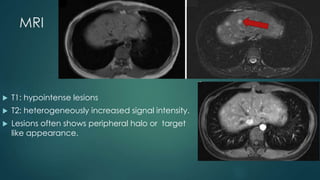

MRI

 T1: hypointense lesions

 T2: heterogeneously increased signal intensity.

 Lesions often shows peripheral halo or target

like appearance.